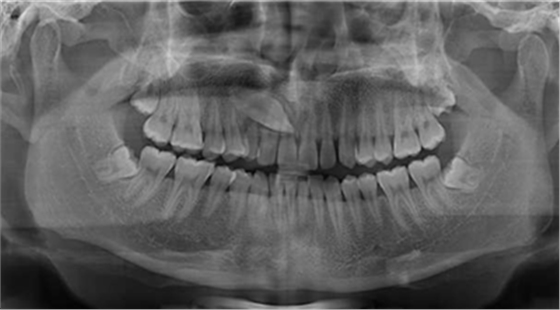

牙片是指牙齿的X线片,也称口内标准片。一张牙片可以显示3-4个牙齿,牙齿在牙片上显示出白色阻射影像。牙片是口腔科应用最广的检查手段,也是最常用的,因为它在牙的治疗前、治疗中和治疗后都有助于诊断和治疗。当然,牙片电离辐射对人体也具有一定的危害。

其面积为3×4平方厘米。一张牙片可以显示3-4个牙齿。牙齿在牙片上显示出白色阻射影像。其中牙釉质阻射最强,牙本质和牙骨质阻射低于牙釉质。牙髓腔呈黑色透明影像,根管口至根尖孔呈逐渐变细的影像。